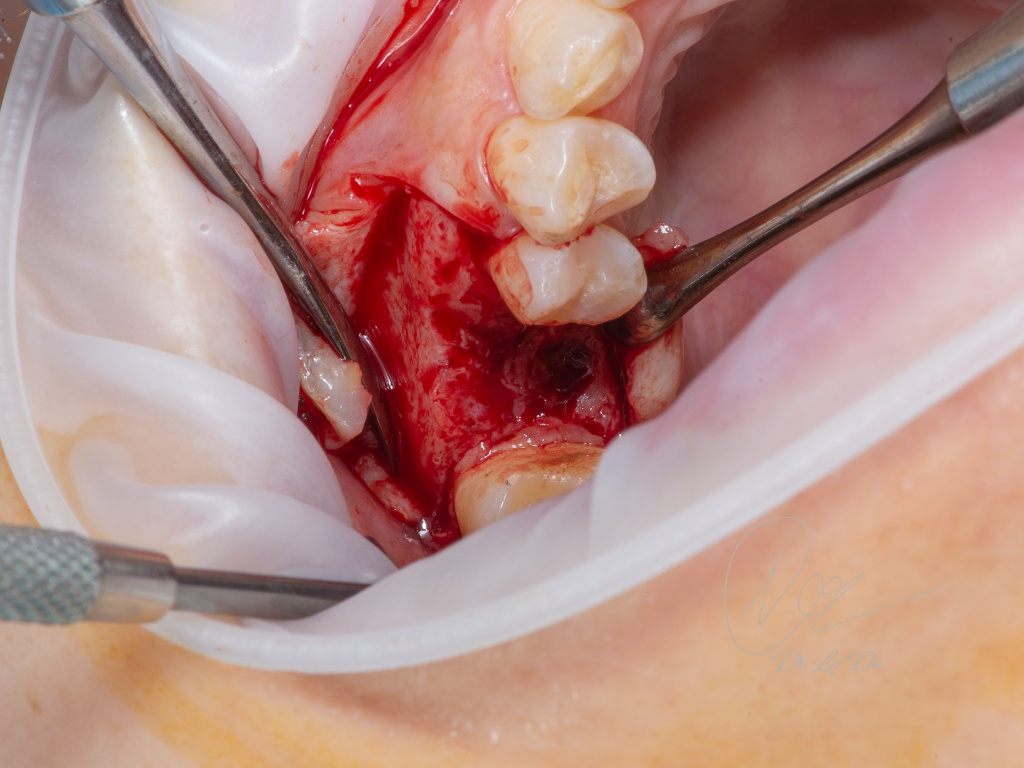

Имплантация AnyRidge с двусторонним закрытым синус-лифтингом.

Осложнения: правосторонний гайморит.

Кейс MINEC: Dr Lu Du